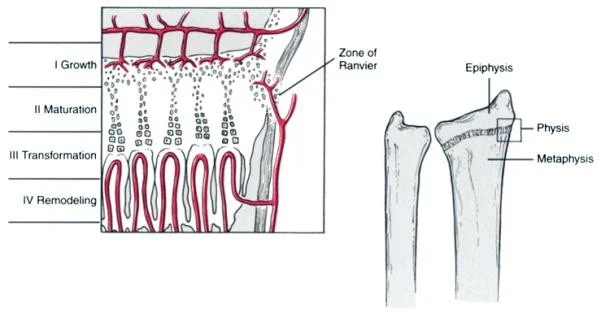

Typical Location

- Metaphysis of long bones

- Upper tibia, proximal or distal femur

- ?Trauma

- Peculiar arrangement of blood vessels

- Terminal arteries twist back in hairpin loops

- Vascular stasis

- Lowered oxygen tension

Age-Specific Vascular Considerations

- In infants, infection may reach Epiphysis

- Anastomoses between metaphyseal and epiphyseal blood vessels